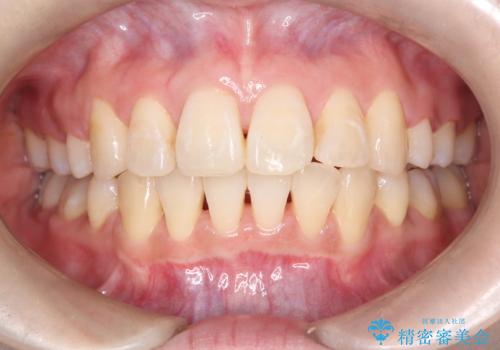

八重歯と正中のズレを解消!目立ちにくいワイヤー矯正で美しい歯並びへ

正中のズレ: 歯を左右対称に移動させることで、上下の歯の中心線を正確に合わせ、顔全体のバランスも改善しました。

治療の結果、長年気にされていた八重歯と正中のズレが解消し、機能的にも整った理想的な歯並びを獲得。目立たない装置で治療を完遂し、自信を持って笑える美しい笑顔を手に入れていただけました。